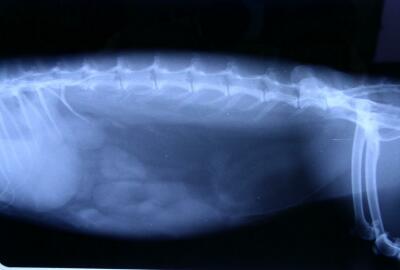

うさぎの「鼓脹症」とは

「鼓脹症」は、胃や腸がガスによって膨らんでしまう状態のことです。

出典:http://exoticpetdata.blog33.fc2.com/blog-entry-4.html

うさぎの胃腸にはたくさんの腸内細菌が住んでいて、食べたものを分解して必要な栄養素を作り出しています。(これを「発酵」といいます。)

発酵の過程でガスが発生しますが、何らかの原因でこのガスが大腸のほうへ抜けていかずに胃腸に充満している状態が「鼓脹症」です。